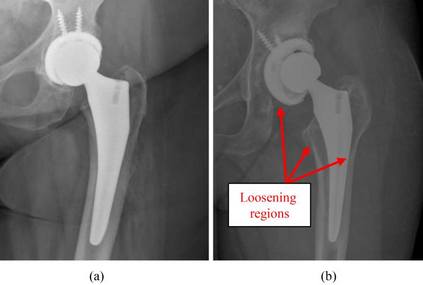

Plain radiography is widely used to detect mechanical loosening of total hip replacement (THR) implants. Currently, radiographs are assessed manually by medical professionals, which may be prone to poor inter and intra observer reliability and low accuracy. Furthermore, manual detection of mechanical loosening of THR implants requires experienced clinicians who might not always be readily available, potentially resulting in delayed diagnosis. In this study, we present a novel, fully automatic and interpretable approach to detect mechanical loosening of THR implants from plain radiographs using deep convolutional neural network (CNN). We trained a CNN on 40 patients anteroposterior hip x rays using five fold cross validation and compared its performance with a high volume board certified orthopaedic surgeon (AFC). To increase the confidence in the machine outcome, we also implemented saliency maps to visualize where the CNN looked at to make a diagnosis. CNN outperformed the orthopaedic surgeon in diagnosing mechanical loosening of THR implants achieving significantly higher sensitively (0.94) than the orthopaedic surgeon (0.53) with the same specificity (0.96). The saliency maps showed that the CNN looked at clinically relevant features to make a diagnosis. Such CNNs can be used for automatic radiologic assessment of mechanical loosening of THR implants to supplement the practitioners decision making process, increasing their diagnostic accuracy, and freeing them to engage in more patient centric care.